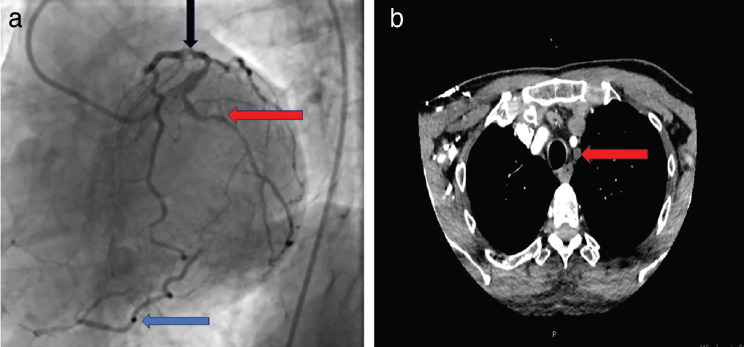

A Novel Approach for the Treatment of Subclavian Steal Syndrome in a Patient Undergoing Coronary Artery Bypass Grafting